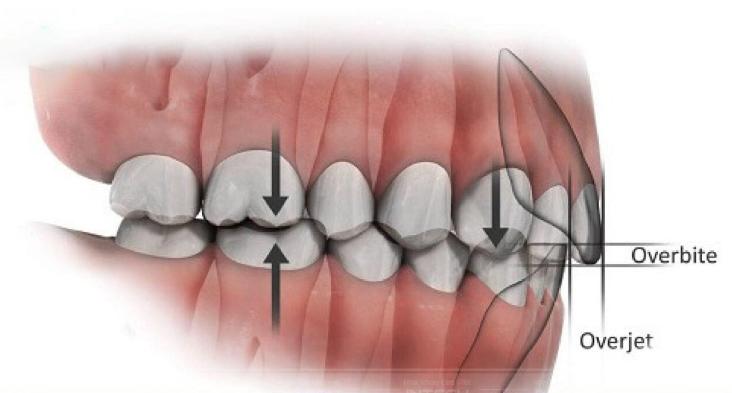

Khớp cắn thường bị hiểu đơn giản là việc các răng chạm vào nhau, nhưng về mặt sinh học, nó là một hệ thống phân phối lực nhai, trong đó mỗi tiếp xúc giữa các múi răng đều đóng vai trò định hướng lực đi theo trục răng và phân bố đều trên toàn bộ cung hàm. Khi khớp cắn không đạt chuẩn, lực nhai sẽ bị lệch, dẫn đến tình trạng một số răng chịu tải quá mức trong khi các răng khác không tham gia đầy đủ vào chức năng, và về lâu dài, điều này có thể gây mòn răng, quá tải khớp thái dương hàm hoặc tạo ra những thay đổi chức năng không mong muốn.

Điểm đáng chú ý là những sai lệch về khớp cắn thường không biểu hiện ngay sau khi tháo niềng mà xuất hiện muộn sau một thời gian sử dụng, khiến nhiều người lầm tưởng rằng kết quả ban đầu là tốt. Trong X-Matrix, khớp cắn không phải là yếu tố được chỉnh sửa ở giai đoạn cuối mà được thiết lập ngay từ đầu thông qua việc xác định tương quan răng hàm, răng nanh, kiểm soát overjet và overbite, đồng thời mô phỏng tiếp xúc khớp cắn trong suốt quá trình dịch chuyển răng, giúp đảm bảo rằng khi kết thúc điều trị, hệ thống nhai đã ở trạng thái cân bằng và ổn định.